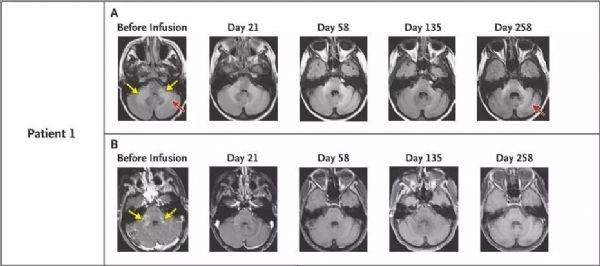

脑脊液中JCV完全清除,临床和影像学表现恢复正常(图片来源 NEJM)

其中一名患者是位32岁的女性,先前因为白血病接受了脐带血移植数,但在癌症治愈了之后,她又被诊断患有进行性多灶性白质脑病(PML),她无法站立或说话清楚。

但在接受一次BKV特异性T细胞注射后,她的神经症状就消失了,三周后便顺利出院了。在第二次和第三次输注后,相隔一个月,患者脑脊液(CSF)中的JCV被完全清除,所有PML病症的迹象都消失了。

脑脊液中JCV彻底清除,病人恢复了独立的活动能力,MRI显示病变区域缩小(图片来源 NEJM)

另一位患者是位患有艾滋病的35岁男子,因为身体在坐着时无法承受体重而只能被抬上担架。他的母亲已经联系了MD安德森询问试验项目,几个月后该患者被诊断出进行性多灶性白质脑病(PML),多年后他因为副作用而停止了侵袭性艾滋病治疗。

在接受四次供体细胞输注后,其体内的病毒被清除,现在,他已经能够用拐杖恢复行走了。